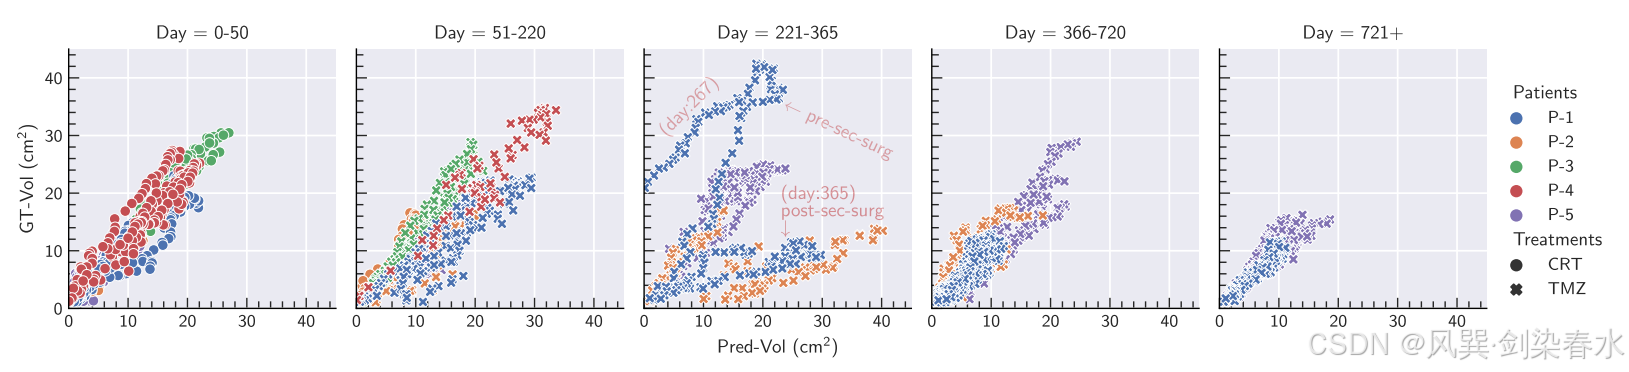

Figure 6 | 基于切片体积估计的肿瘤生长预测评价,用于未来治疗和天数:该图表详细展示了 GT-Vol 和 Pred-Vol 在不同日期范围、测试患者及治疗类型之间的关系。每个关系图对应一个目标日期范围,患者通过颜色区分,不同的标记表示不同的治疗类型。值得注意的是,这些图表中没有排除涉及第二次手术(术前和术后)的案例;相反,在日期为221至365的图表中,本文通过注释来突出显示这些情况;